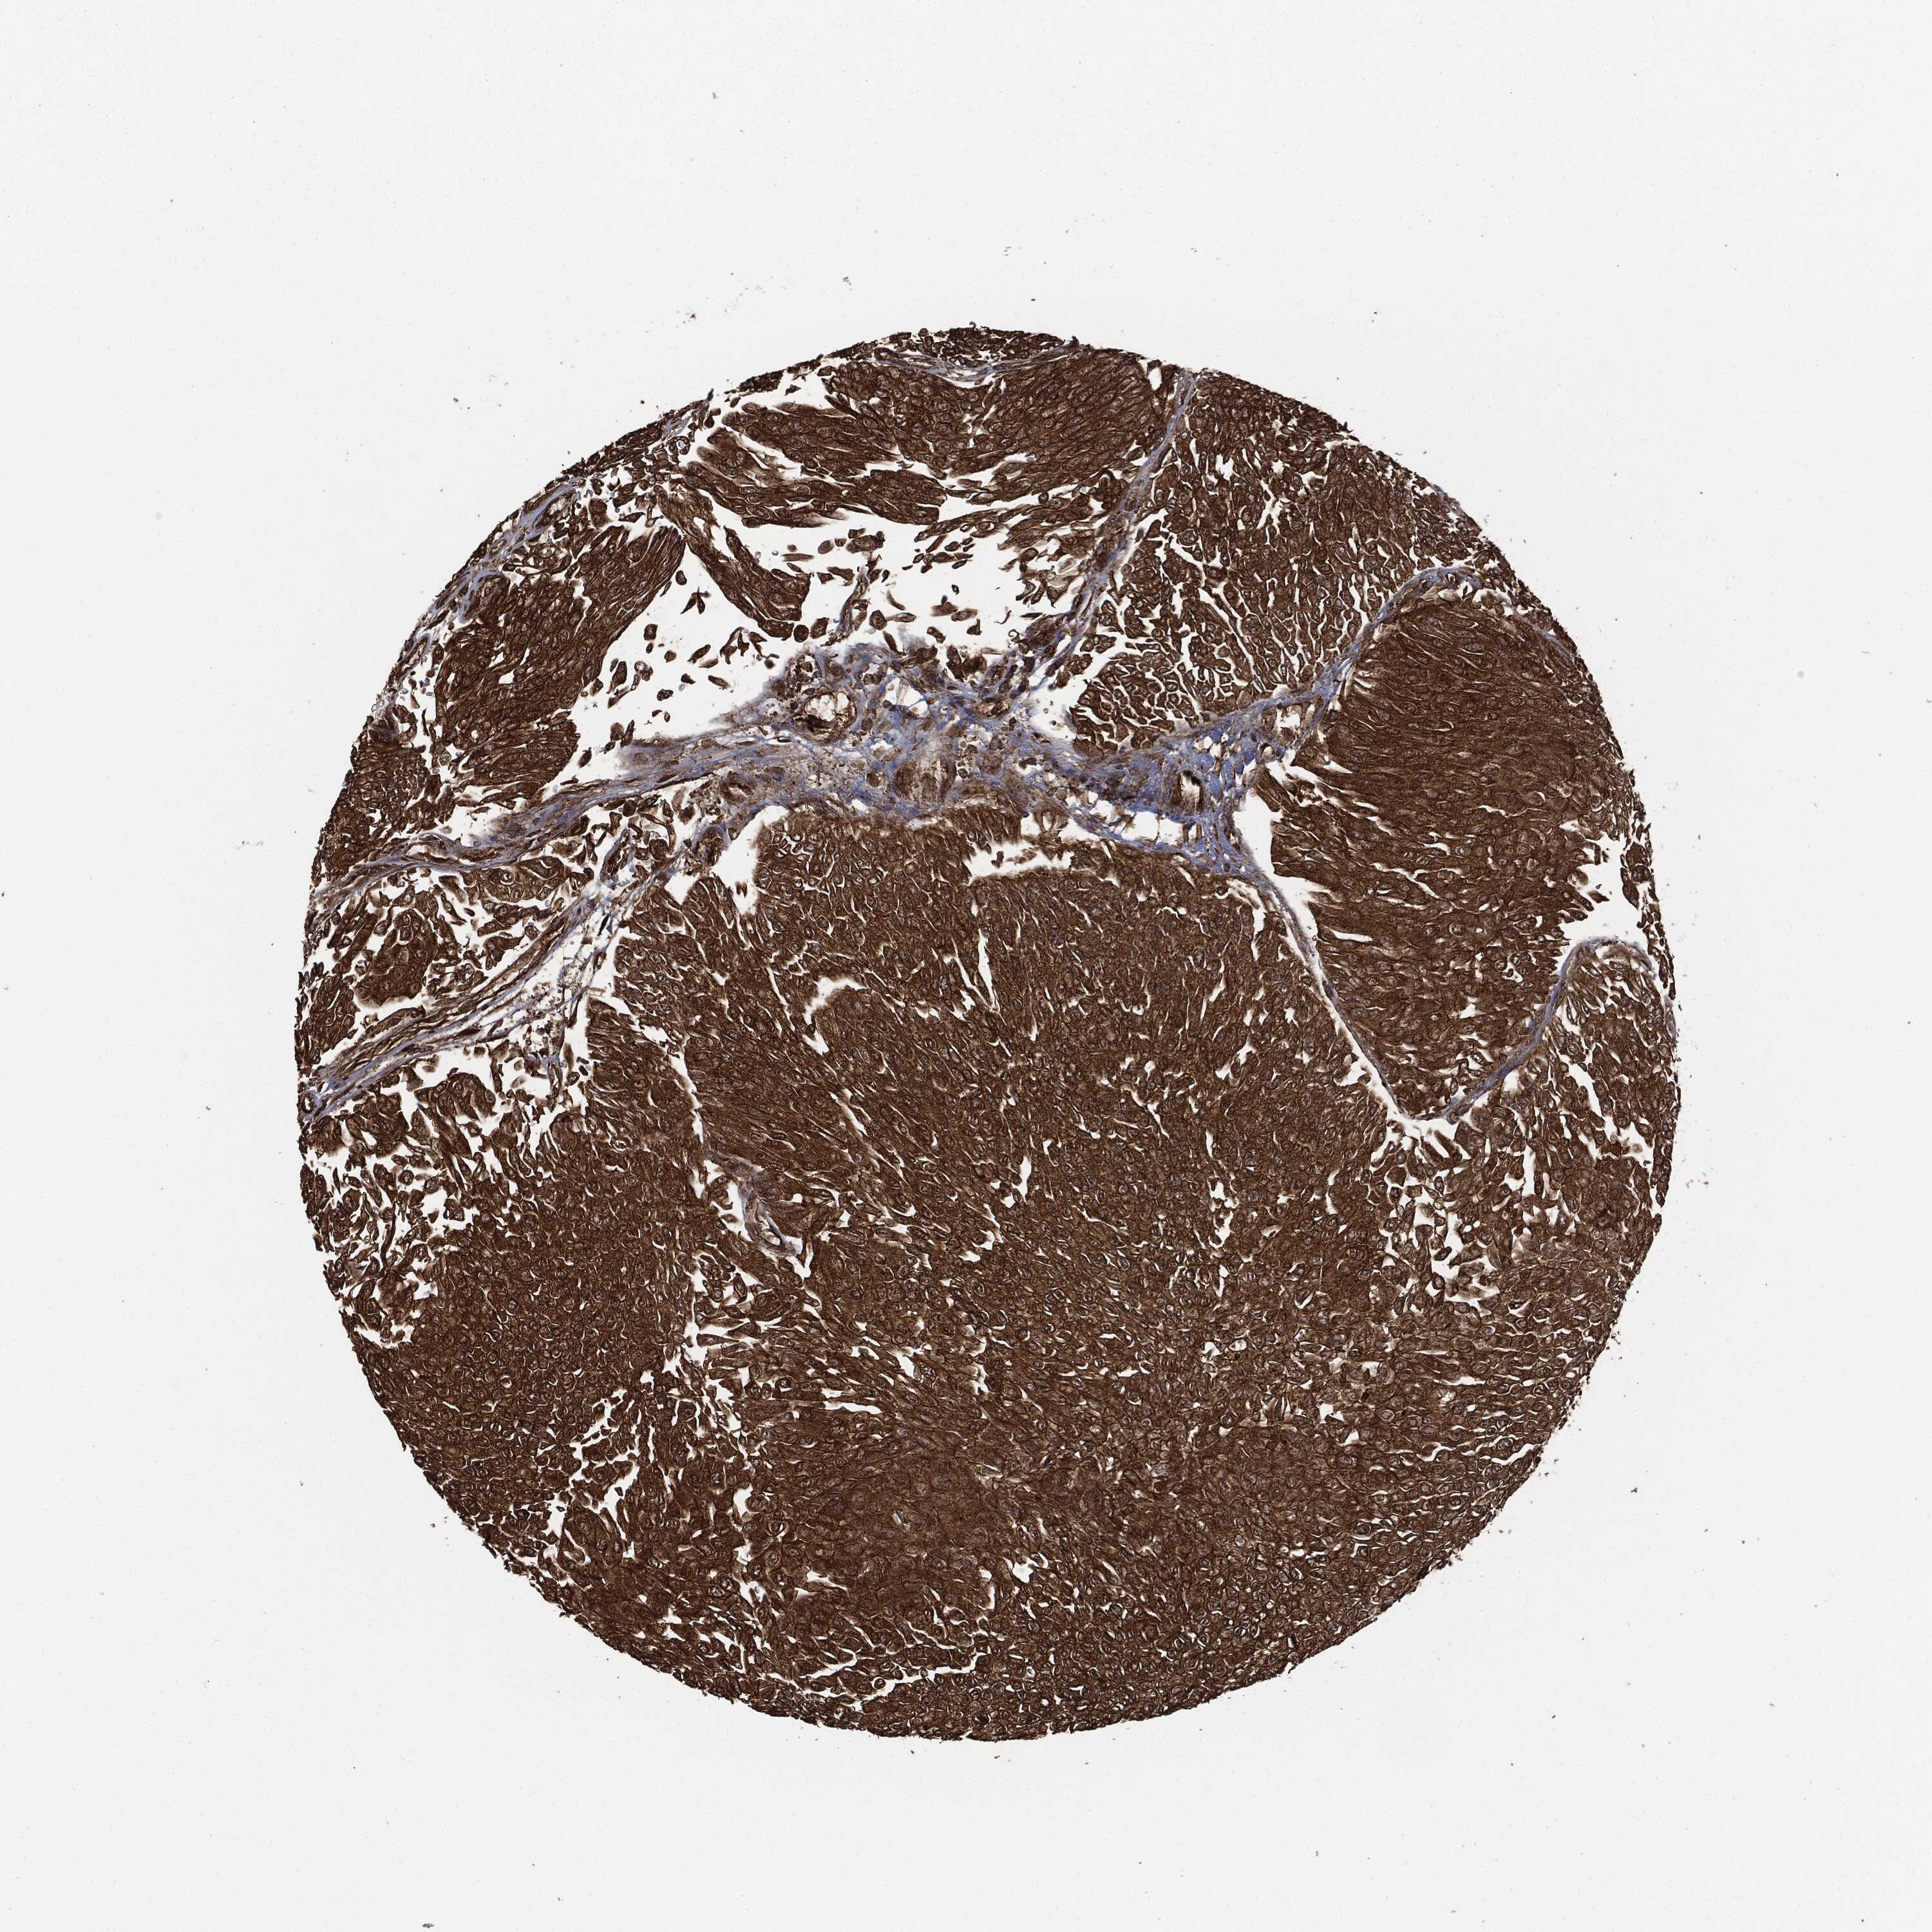

UROTHELIAL CANCER - Protein expressioni

A mouse-over function shows sample information and annotation data. Click on an image to view it in a full screen mode. Samples can be filtered based on level of antibody staining by selecting one or several of the following categories: high, medium, low and not detected. The assay and annotation is described here.

Note that samples used for immunohistochemistry by the Human Protein Atlas do not correspond to samples in the TCGA dataset.

Antibody stainingi

Antibody staining in the annotated cell types in the current human tissue is reported as not detected, low, medium, or high, based on conventional immunohistochemistry profiling in selected tissues. This score is based on the combination of the staining intensity and fraction of stained cells.

Each image is clickable and will lead to virtual microscopy that enables deeper exploration of all samples and also displays staining intensity scores, fraction scores and subcellular localization as well as patient and tissue information for each sample.

HPA049830

CAB002015

CAB080330

CAB080331

CAB080332

Urothelial carcinoma, High grade

Urothelial carcinoma, NOS

Urothelial carcinoma, Low grade

Adenocarcinoma, NOS